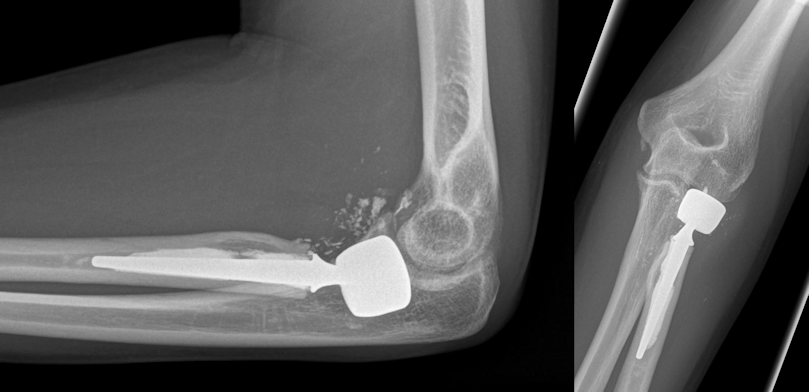

Figure 3: Postoperative radiographs after implantation of a cemented bipolar radial head prosthesis

Figure 4: Same patient 12 months after the injury: grade 1 degenerative changes and heterotopic ossifications at the elbow, but good to excellent functional results. No signs of loosening of the radial head prosthesis.